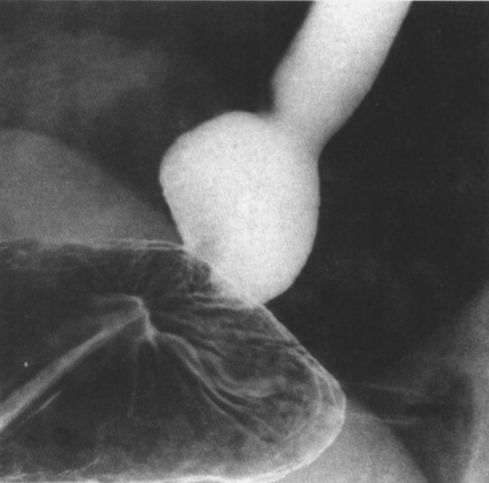

贲门失弛缓:鸟嘴征。

中度贲门失迟缓

重度贲门失迟缓